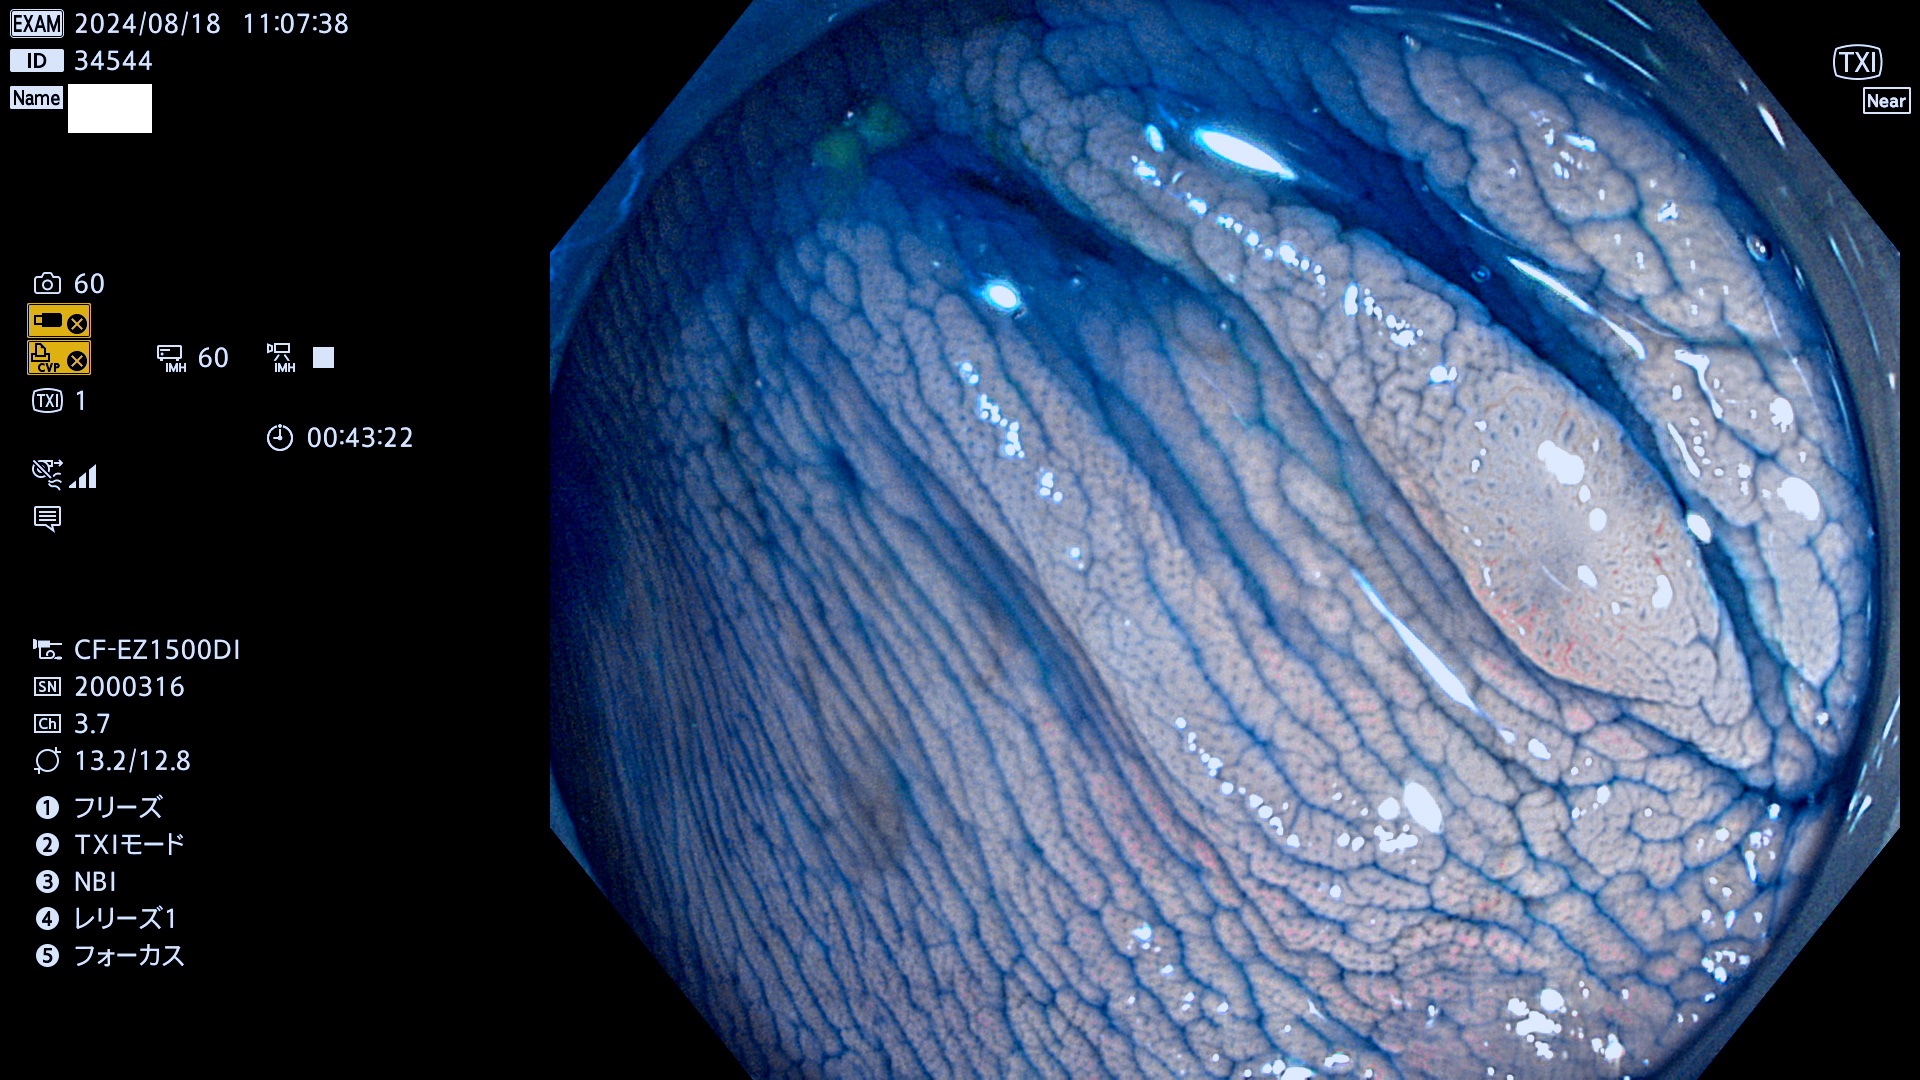

今週のUb、Uc型腺腫

完全に平坦な物をUb、陥凹している物をUcと呼びます。最も発見が難しく危険な病変です。

抽出の対象期間 2024年8月15日〜8月18の4日間(33件の検査)7件 (7/33=21%)